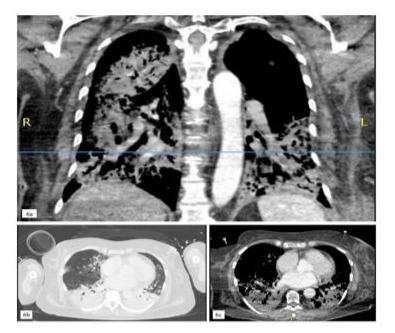

Figure 6: Pulmonary imaging findings presenting an acute, ICIinduced pneumonitis with a bacterial superinfection (6a-c).

After the third dose of pembrolizumab, the patient developed neutropenic sepsis and was admitted with severe acute respiratory distress syndrome (ARDS), characterized by a PaO2/FiO2 ratio of less than 70. A diagnostic workup revealed influenza-A pneumonia with bacterial superinfection by staphylococcus aureus and a high suspicion of autoimmune pneumonitis (Figure 6). Despite anti-infective treatment, the patient’s condition deteriorated, necessitating endotracheal intubation and invasive mechanical ventilation.